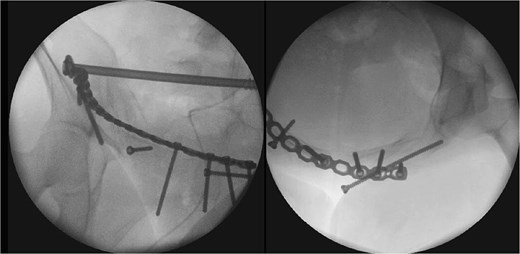

After one week of monitoring in the ICU, where she remained stable without need for ventilatory support, the patient was transferred to the ward. She then underwent the first surgical stage in supine position. Anterior pelvic fixation (Fig. 3a) was performed via a Pfannenstiel anterior approach combined with the first window of the right ilioinguinal approach, using a 3.5-mm reconstruction plate on the right anterior column crossing the pubic symphysis and a 3.5-mm retrograde screw in the left anterior column, inserted through the same Pfannenstiel access. During the same procedure, a 7.3-mm trans-sacral screw was placed in S1 on the right to stabilize the sacral fracture (Fig. 4). The surgery lasted ⁓3 h, and the patient was transferred to the semi-intensive care unit for postoperative monitoring.

The second surgical stage was performed under general anesthesia two weeks later, delayed by one week of hemodynamic monitoring and subsequent unavailability of surgical materials. In supine position, the left sacroiliac joint was fixed with two 7.3-mm cannulated screws, and a seroma in the Pfannenstiel approach was drained. Subsequently, with the patient repositioned in prone position (Fig. 3b), lumbopelvic fixation from L4-L5-S1 to the posterior ilium (EIPS) was performed using rods and pedicle screws (Fig. 5). This procedure lasted ⁓3 h. At this point, ˃3 weeks post-trauma, anatomical reduction was significantly hindered by early consolidation and fibrosis at the fracture sites, requiring extensive maneuvers. The patient was transferred to the ICU, extubated without complications the following day, and returned to the ward after two days, receiving hospital discharge thereafter.